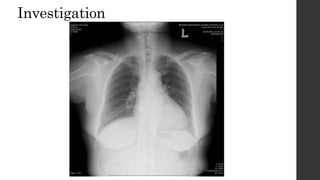

Investigation

• No gold standard for diagnosis

• Radiographs : chest radiograph and cervical spine radiographs

 cervical rib

 prominent C7 transverse process

 low lying shoulder girdle

 Pancoast tumor

Investigation • No goldstandard for diagnosis • Radiographs : chest radiograph and cervical spine radiographs  cervical rib  prominent C7 transverse process  low lying shoulder girdle  Pancoast tumor • Three-dimensional imaging CT and MRI • Nerve conduction studies • Vascular studies • Angiography